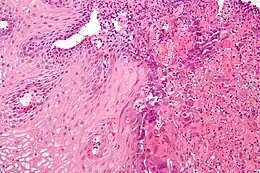

L’œsophagite est une inflammation de l’œsophage. Elle peut être aiguë ou chronique.

La réalisation d'une fibroscopie œsophagienne est indispensable pour affirmer le diagnostic. Il existe une classification des œsophagites selon leur aspect macroscopique (conférence de consensus franco-belge, 1999).